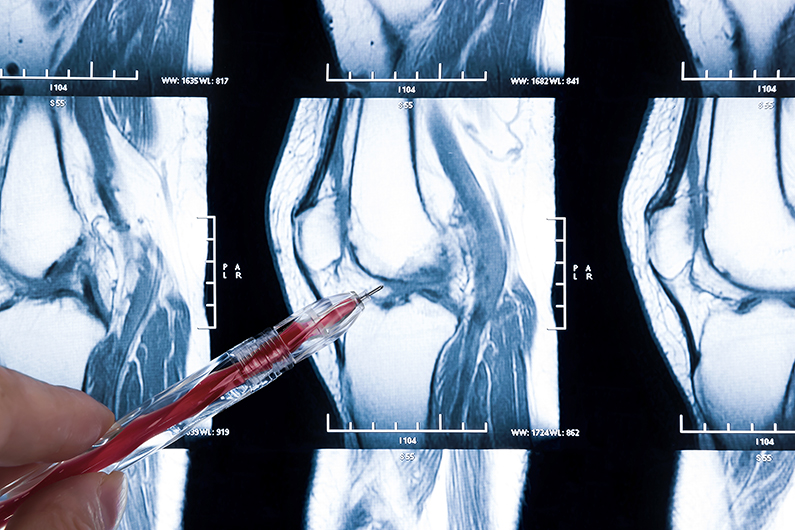

NIH Clinical Center researchers seek 18-55 year olds with kneecap pain (patellofemoral or anterior knee pain) for a 2-visit outpatient research study. We are studying how muscle weakness around the knee may lead to changes in kneecap motion and pain. Compensation provided. Refer to Study # 13-CC-0099.